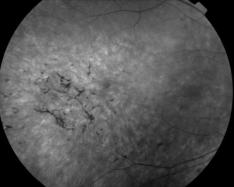

RETINOPATHIE PIGMENTAIRE